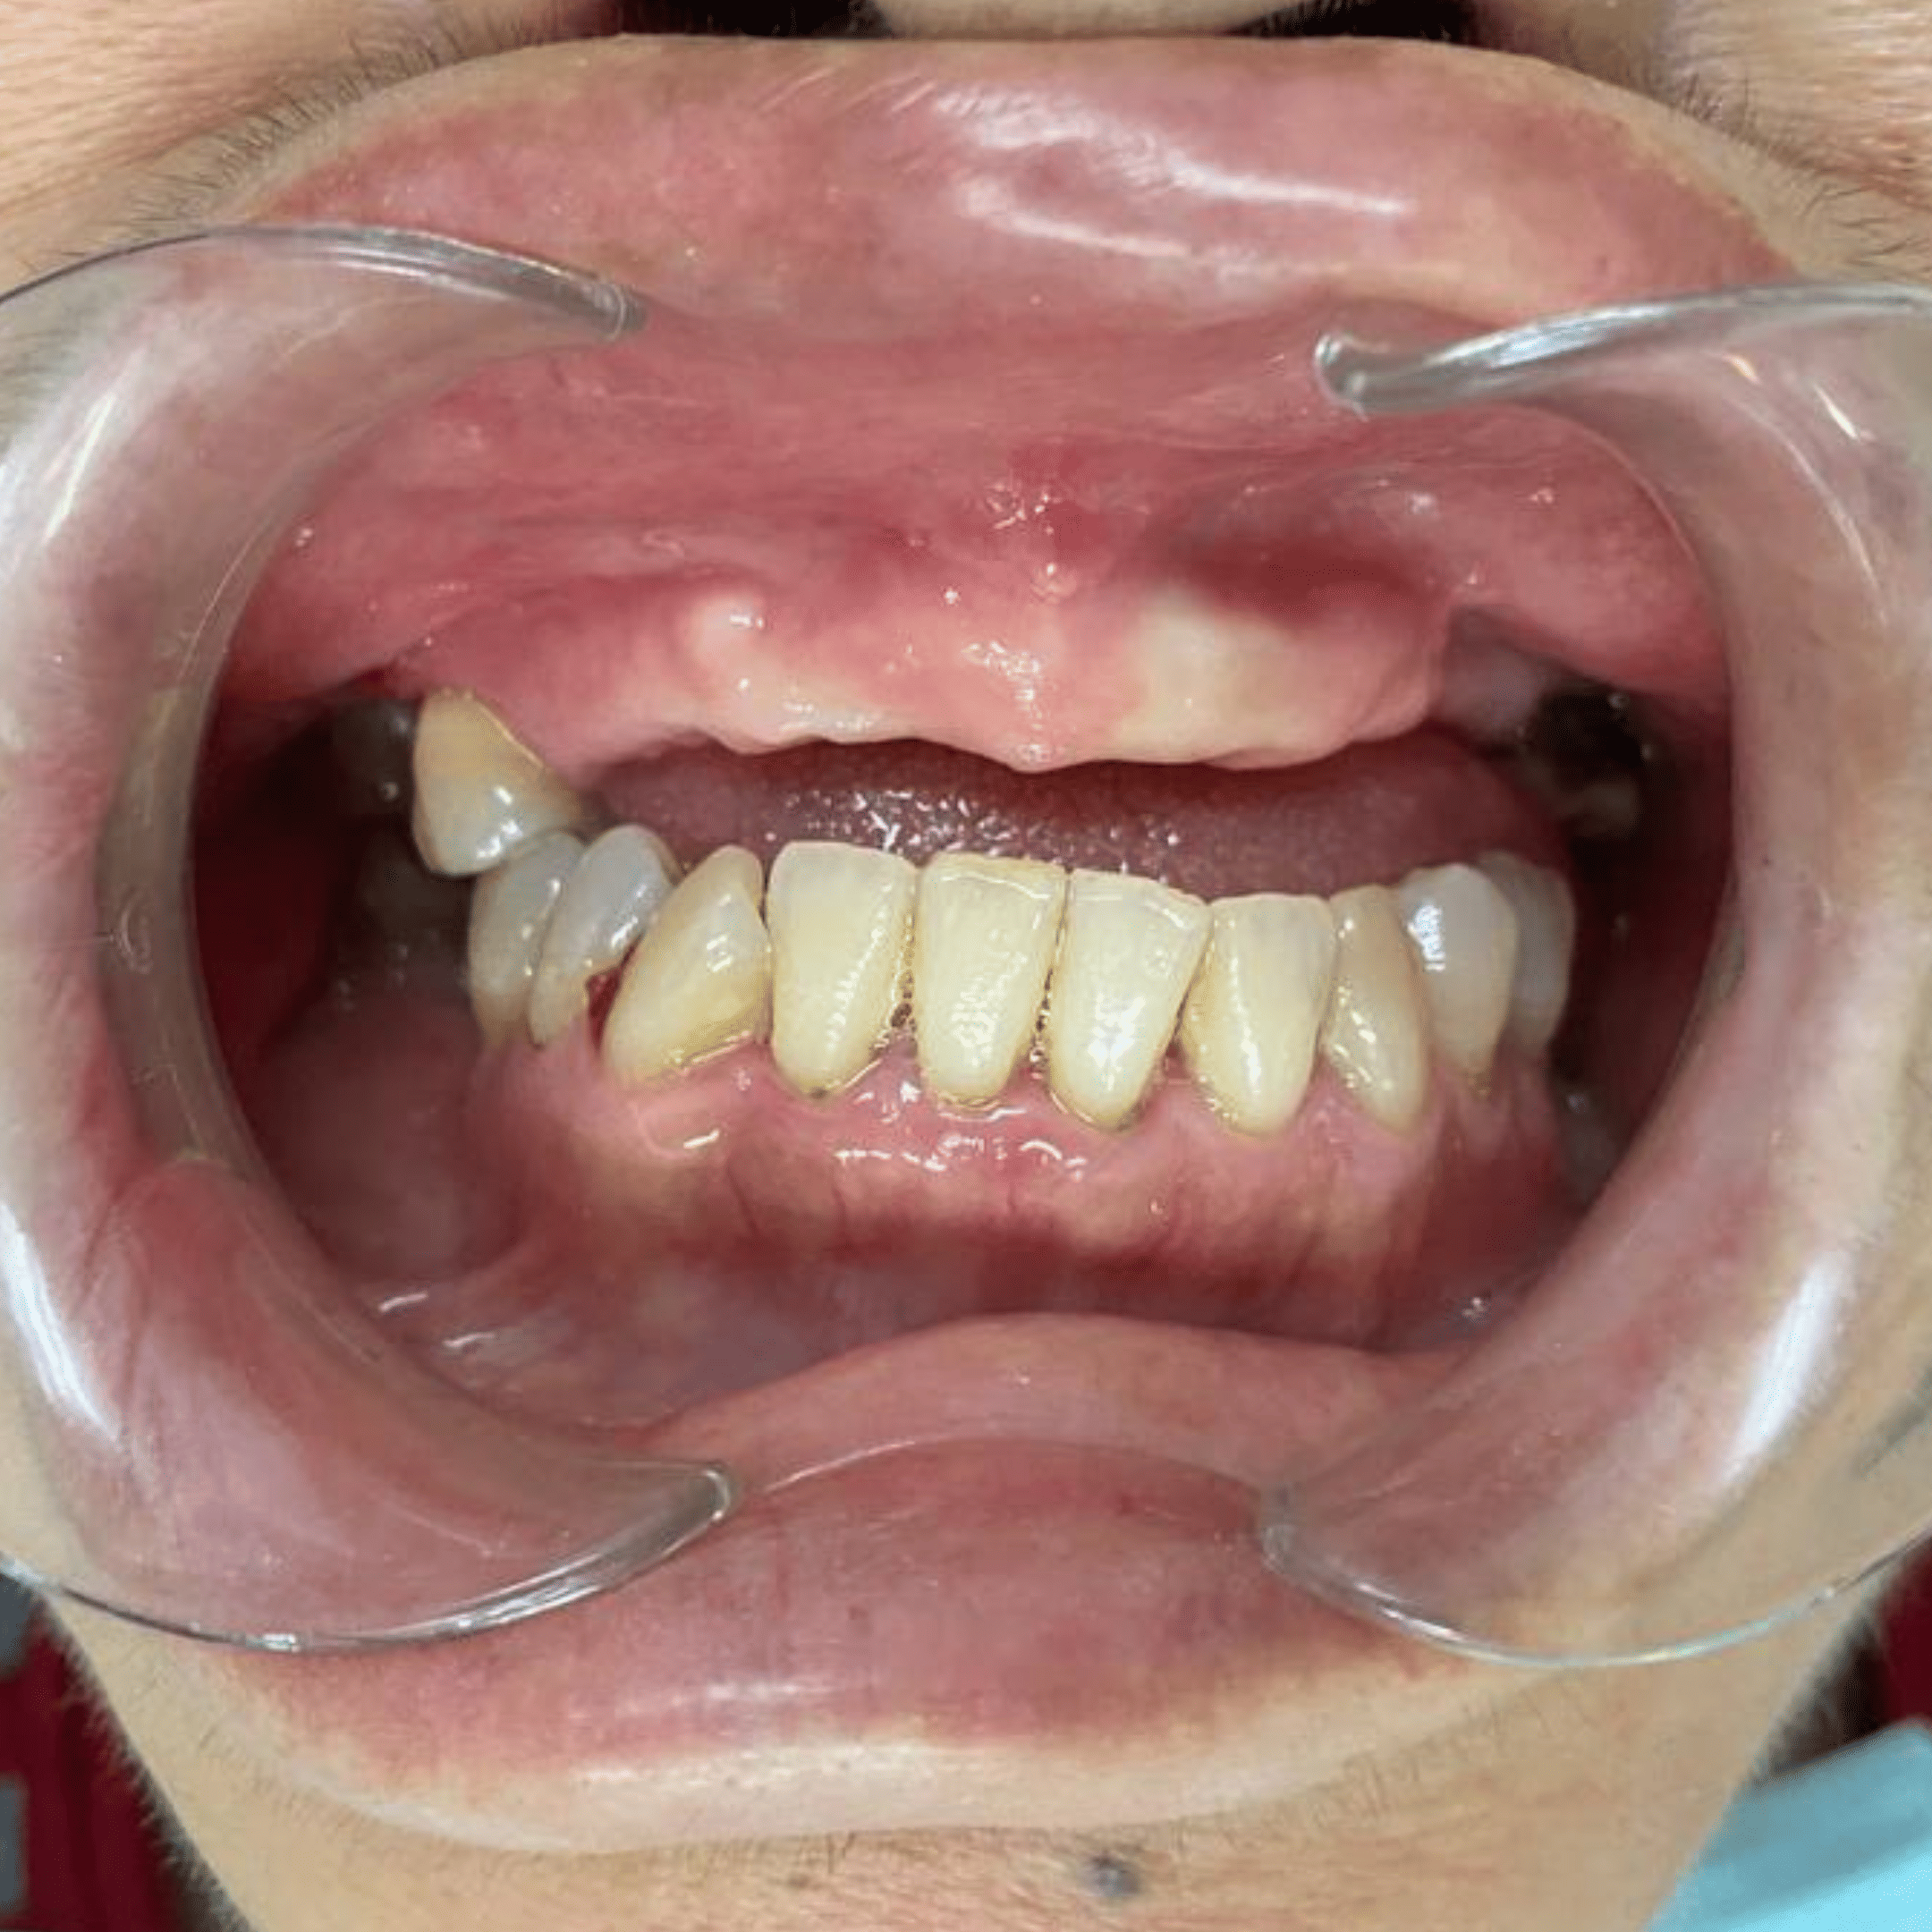

Before & After

📸 Before: Visible gap between teeth

📸 After: Implant crown blends naturally with other teeth